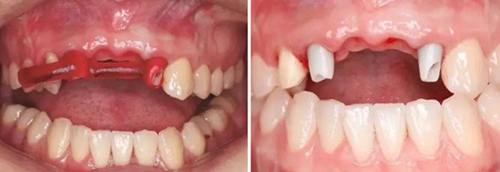

圖1 植骨術(shù)前口內(nèi)正面觀 圖2 植骨術(shù)前口內(nèi)頜面觀

圖5 制取的髂嵴部骨塊 圖6 植骨術(shù)前牙槽嵴頂切開翻瓣

圖7 受植區(qū)固定髂骨骨塊 圖8 自體骨屑與人工骨粉混合后充填植骨間隙

圖9 嚴(yán)密縫合創(chuàng)口 圖10 植骨后拆線

圖11 植骨后6月種植術(shù)前 圖12 種植術(shù)前翻瓣后見少量鈦釘螺紋暴露